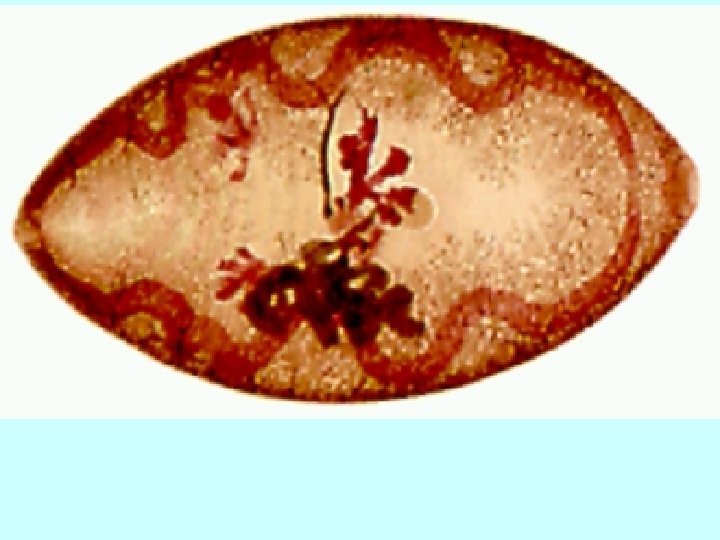

A cross-section of Paragonimus sp in lungs. The tegument is covered with spines which

A cross-section of Paragonimus sp in lungs. The tegument is covered with spines which appear reddish in colour. The vitellaria are dark bodies scattered along the periphery. One of the intestinal caeca is also visible.